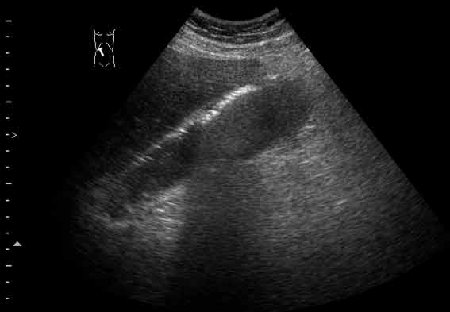

Острый эмфизематозный холецистит

Острый эмфизематозный холецистит. В желчном пузыре определяется газ, он располагается при малейшем изменении положения тела в самой верхней точке желчного пузыря. Газ в пузыре (СО2) является продуктом жизнедеятельности бактерий и при отсутствии ятрогенных вмешательств чаще всего указывает на эмфизематозное воспаление.